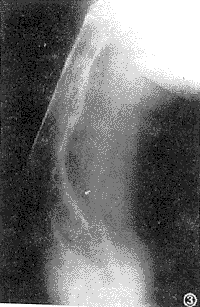

亦称棕色瘤,属甲状旁腺机能亢进有特殊诊断意义的征象。表现为大小不等、单发或多发的囊样透明区,边界较清楚。较大的骨缺损,不仅有膨胀样表现,而且容易骨折,有时病灶内可呈多房样改变,颇似巨细胞瘤。发生于下颌骨者,还应与造釉细胞瘤鉴别。纤维囊性骨炎,以长管骨多见,还可见于椎体、髂骨和肋骨等。原发性甲状旁腺机能亢进原发病因解除后,棕色瘤所致骨缺损,可以自行修复。所谓棕色瘤(brown tumor),是因破骨细胞的数量和活性增加,致使局部骨质溶解吸收,代之以增生的纤维组织。骨溶解区不断扩大,形成囊样骨缺损,其内的纤维组织变性并出血,囊内的组织即呈棕(褐)色,故得名。棕色瘤很少发生于儿童(图3)。

图3 股骨远端膨大,内示大小不等的囊样透亮区,干骺端者呈纱网状改变。普遍性骨质疏松,并多处不全骨折